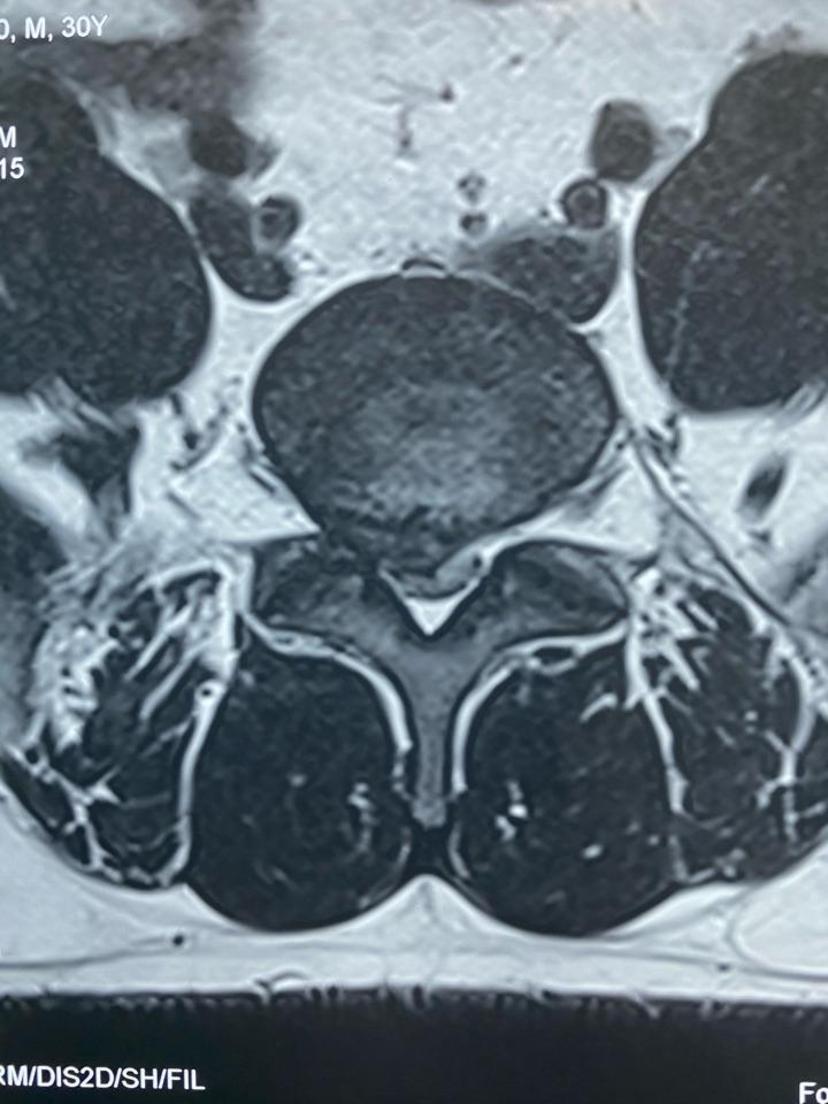

腰5-骶1巨大椎间盘突出、多日卧床行走困难,微创后第二天正常行走,总共住院三晚上!腰5-骶1巨大椎间盘突出右侧神经严重受压取出的压迫物术后右腿痛麻消失,可正常抬腿手术当天切口情况